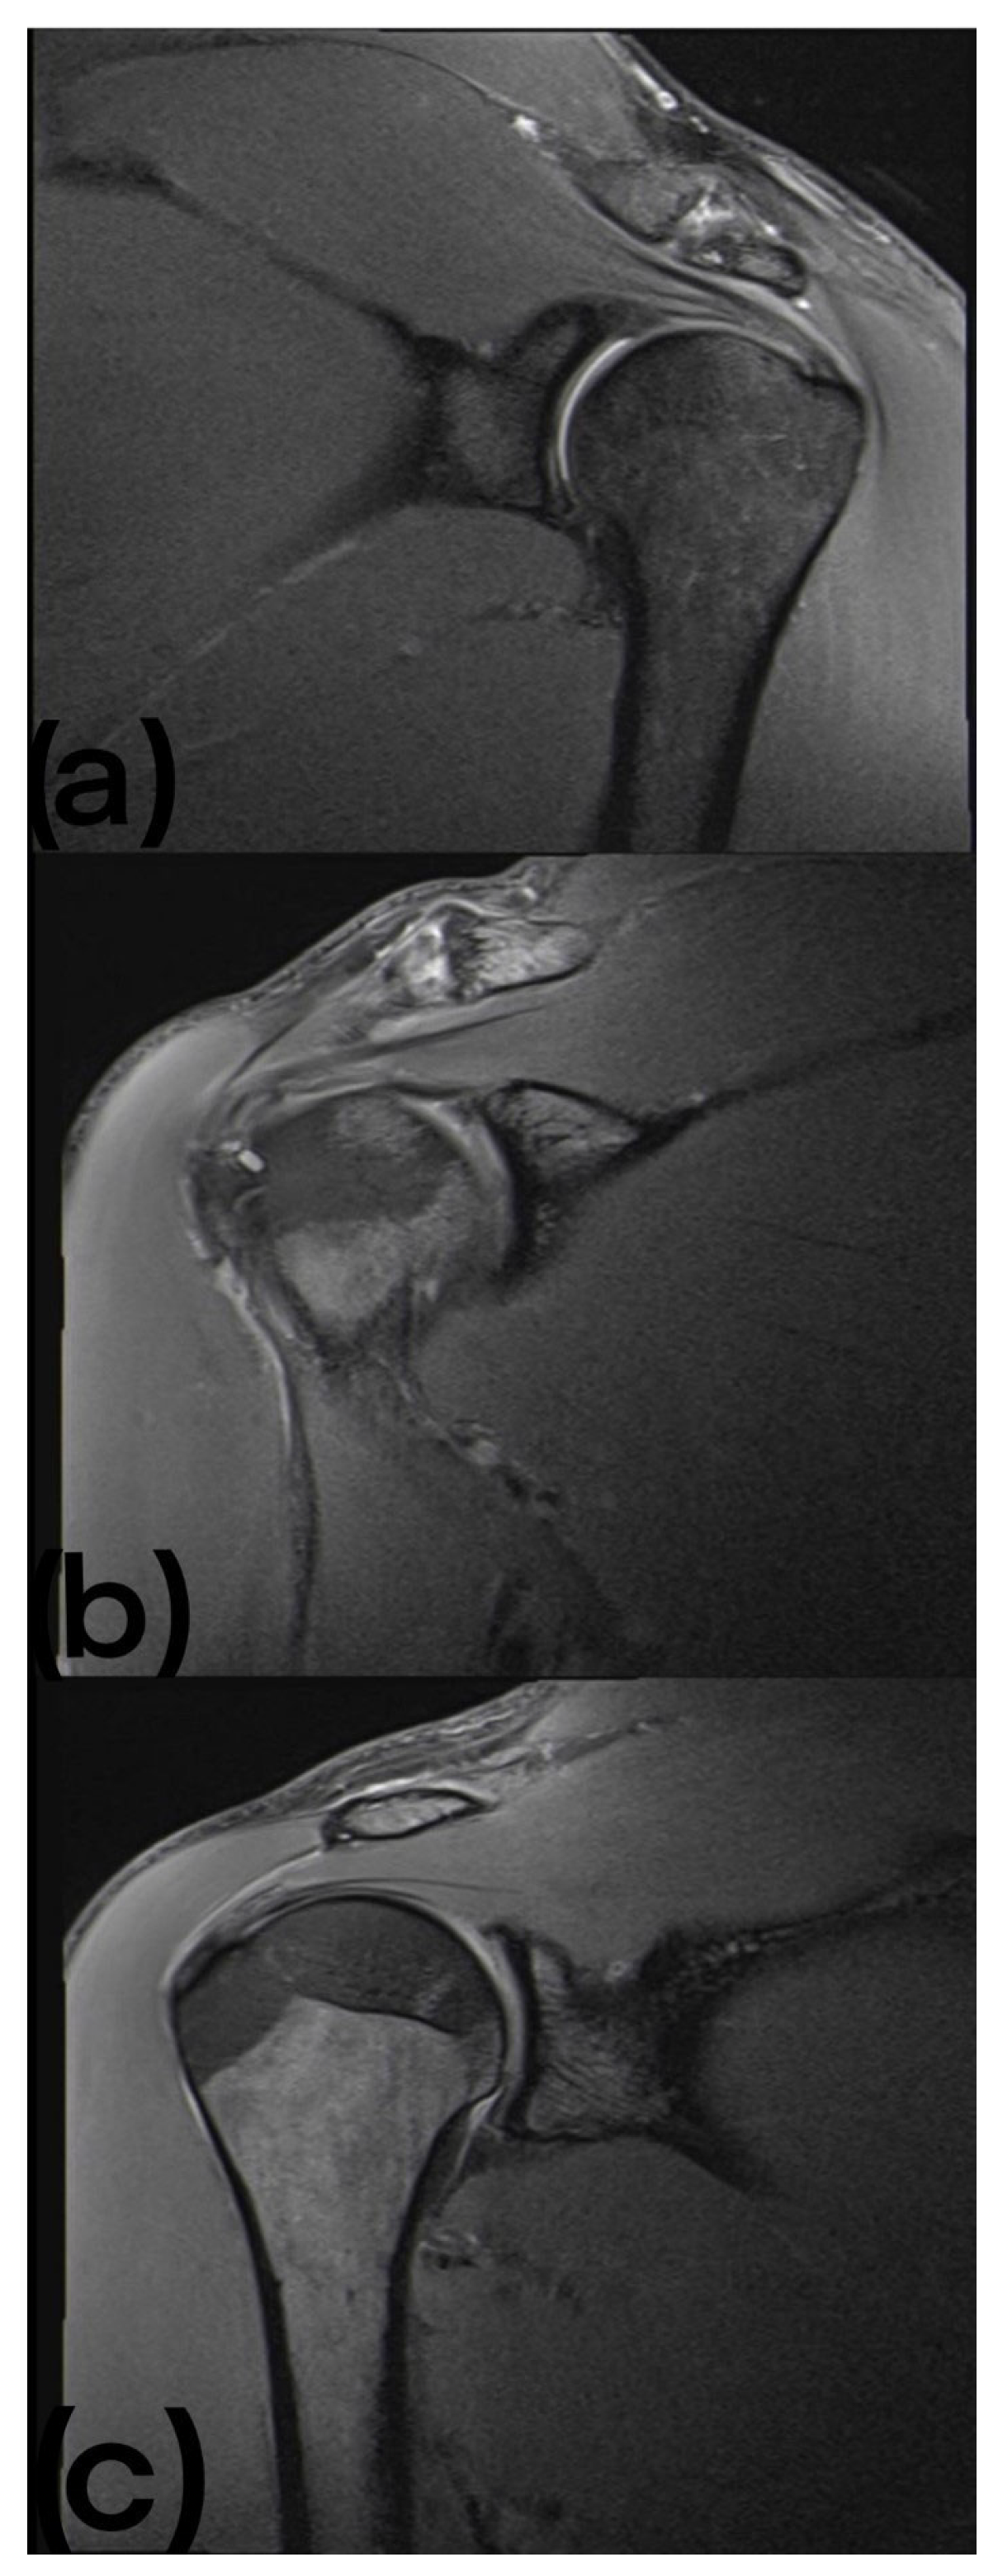

Thirty-five abnormalities were found in the MRI images. These were divided into two tendinopathies of the supraspinatus tendon (9.1%), one labrum change (4.5%), three humeral tuberosity cysts (13.6%), fourteen AC joint hypertrophies (63.6%), five AC joint osteophytes (22.7%), and ten signs of inflammation of the AC joint (45.5%) (see Figure 1).

Figure 1. (a) MRI of the left shoulder showing edematous changes at the AC joint. (b) MRI of the right shoulder showing small cystic resorptions near the intertubercular sulcus. (c) MRI of the right shoulder of the same participant shown in (b), showing low attachment tendinopathy of the supraspinatus tendon.

In more than half of the shoulders examined, namely 63.6%, hypertrophy of the joint could be detected.